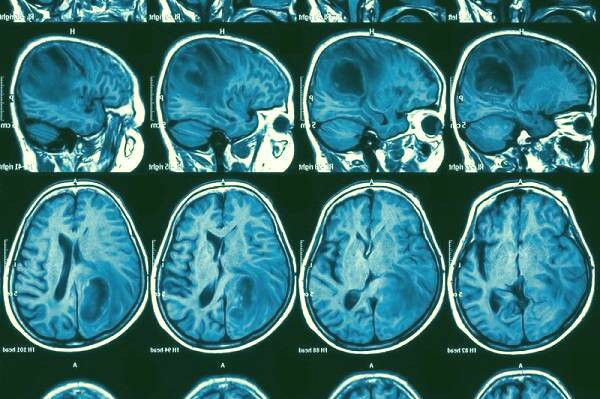

تصویربرداری فناوری نانو تکنولوژی

روش های تصویربرداری در حال حاضر می توانند طیف وسیعی از سرطان ها را تشخیص دهند. این امر اغلب سال ها طول می کشد:تا این زمان, هزاران سلول تکثیر می کنند و یا شاید پخش هم شوند.

حتی در مواردی که قابل رویت است, ماهیت تومور - بدخیم یا خوش خیم - و ویژگی هایی که ممکن است به یک درمان خاص پاسخ دهد, باید از طریق نمونه برداری تهاجمی ارزیابی شود.

به جای آن تصور کنید که اگر سلول های سرطانی یا حتی پیش سرطانی با دستگاه های اسکن معمولی تشخیص و برچسب گذاری شوند.

برای مثال, آنتی بادی های موجود در سلول های سرطانی می توانند بر روی نانوذرات پیدا شوند، تا زمانی که تصاویر تشدید مغناطیسی (mri) یا توموگرافی محاسبه شده (ct) مورد استفاده قرار گیرند, یک سیگنال کنتراست بالا ایجاد شود.

بنابراین نانوتکنولوژی می تواند تجسم کردن نشانگرهای مولکولی باشد که مراحل و انواع سرطان ها را شناسایی می کنند و به پزشکان اجازه می دهند سلول ها و مولکول های غیرقابل کشف را از طریق تصویربرداری معمول ببینند.